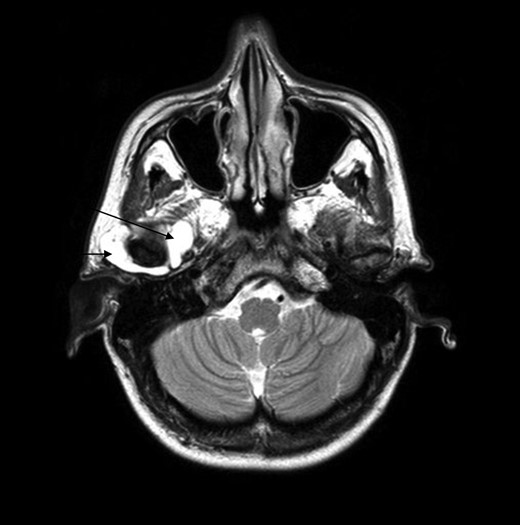

After clinical examination an magnetic resonance imaging (MRI) scan was done. A large joint effusion in the right TMJ was found and interpreted as an arthritis (Fig. 2).

MRI scan, the arrows point out the huge effusion medial and lateral of the right TMJ.